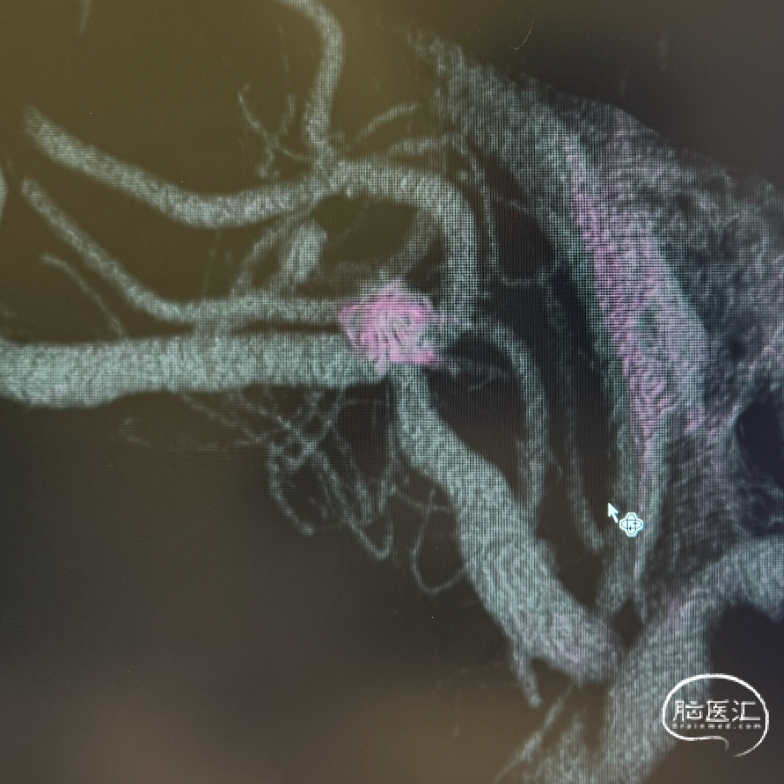

三维旋转图像:左侧大脑中动脉早额支起始部囊性动脉瘤。

动脉瘤参数:最大径4.4mm,瘤高3.5mm,瘤颈宽3.5mm,载瘤动脉直径1.3mm。

术后三维重建及WEB™融合后图像,可见WEB™贴壁良好。

WEB™装置型号匹配:根据动脉瘤参数(3.8×3.5mm),选择WEB™ SL 4mm*2mm型号,其设计特点能适应分叉部解剖,但需注意成角可能影响装置展开。术前需通过三维影像精确测量瘤颈宽度与瘤体深度,避免因尺寸偏差导致贴壁不良或移位。

WEB™释放的实时评估:在成角部位,装置展开易受血流冲击影响。需通过多角度造影动态观察WEB™形态,重点确认瘤颈覆盖是否完全、尾端是否充分展开。本例通过反复调整,最终实现装置稳定贴壁,术后利用西门子自带多容积三维重建,分析扰流装置的位置,证实了技术操作的可靠性。